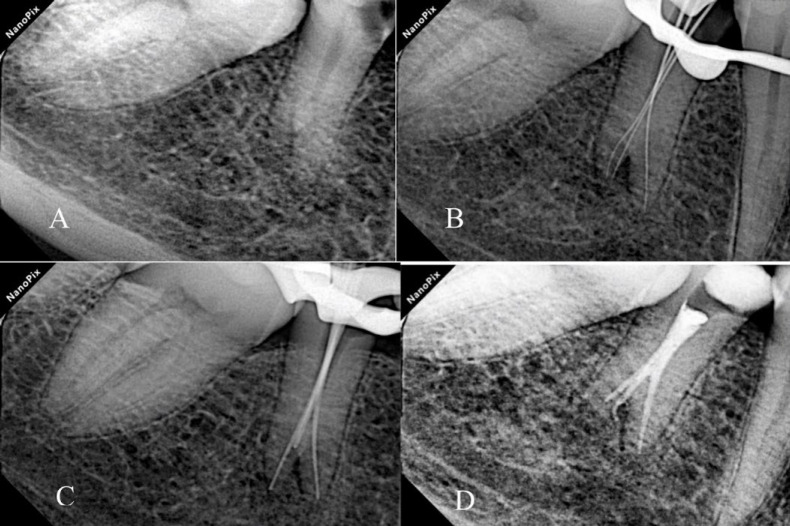

全面了解根管形态是成功进行牙髓治疗的关键。尽管有报道称下颌第二前磨牙的根尖通常只有一个根管,但在本病例中,我们却发现一颗下颌第二前磨牙有三个根管,而且形态呈陶土状。一名患者被转诊至马什哈德牙科学院牙髓科,主诉是下颌右侧第二前磨牙疼痛。牙髓坏死和慢性根尖牙周炎的诊断已经确定。最初的 X 光片显示她的前臼齿有两个牙根。然而,在锥形束计算机断层扫描的辅助下,确诊有三个根管。使用牙科手术显微镜成功地完成了根管治疗过程。使用锥形束计算机断层扫描和牙科手术显微镜极大地促进了牙齿形态的确定,并成功地进行了非手术根管治疗。

A complete understanding of canal morphology is essential to achieve successful endodontic treatment. Although mandibular second premolars are reported to have usually only one root canal at the apex, in this case we reported a mandibular second premolar with three root canals and taurodont morphology. A patient was referred to the endodontic department at Mashhad Faculty of Dentistry with a chief complaint of pain in her mandibular right second premolar tooth. The diagnosis of pulpal necrosis and chronic apical periodontitis was established. The initial radiograph showed a taurodont premolar with two roots. However, with cone-beam computed tomography assistance, three root canals were confirmed. The root canal treatment process was successfully managed with a dental operating microscope. Using cone-beam computed tomography and a dental operating microscope greatly facilitated the determination of tooth morphology and successful following nonsurgical endodontic treatment.